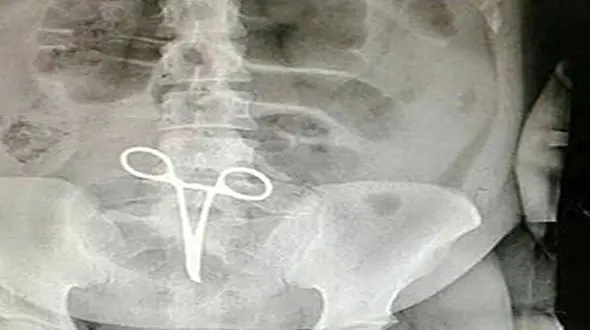

حوادث رکنا: دختر جوانی که قیچی جراحی در شکمش جا مانده بود به علت عفونت درگذشت.